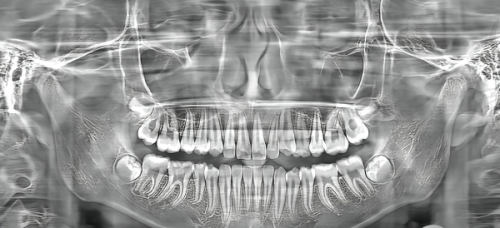

Twin Block矫正器(简称TB),是儿童青少年矫正“小下巴”“龅牙”的热门工具。它属于功能性矫治器,并非传统的固定托槽。其核心是通过上下颌垫斜面引导下颌前移,从而刺激骨骼改建。

核心作用显著:一方面,70°斜面颌垫,孩子每天佩戴18小时,可让下巴前移3 - 5mm,有效重塑侧脸线条。另一方面,它能矫正口呼吸、咬唇等不良习惯,让口周肌肉正常发力。

解决下巴后缩:如果孩子闭嘴时下唇包住上唇,侧面看下巴“消失”,就可能存在下巴后缩问题。Twin Block矫正器通过斜面引导下颌前伸,刺激髁突(下颌关节)生长,SNB角平均增加4.2°,有效解决下巴后缩。

矫正深覆合:当孩子上牙盖住下牙超过1/3,导致“露龈笑”时,就可以使用该矫正器。方法是分阶段磨低颌垫,让后牙自然萌出,重建咬合高度。